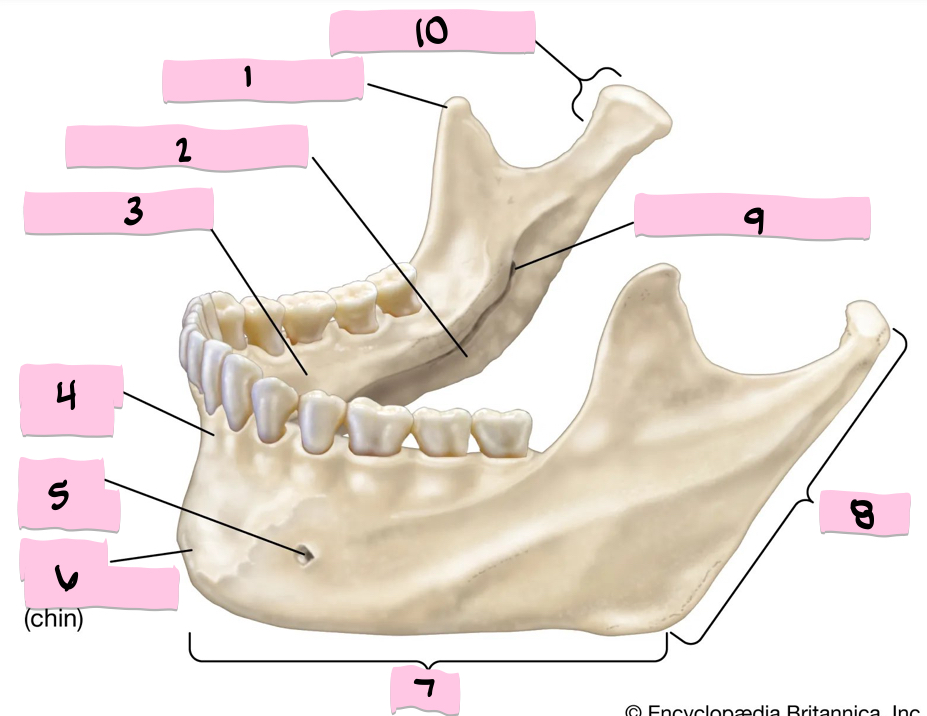

What is 1 pointing to?

Coronoid process

What is 2 pointing to?

Submandibular fossa

What is 3 pointing to?

Sublingual fossa

What is 4 pointing to?

Alveolar process

What is 5 pointing to?

Mental foramen

What is 6 pointing to?

Mental protuberance

What is 7 pointing to?

Body

What is 8 pointing to?

Ramus

What is 9 pointing to?

Mandibular foramen

What is 10 pointing to?

Condylar process